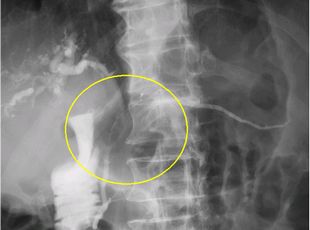

●ERCP(内視鏡的逆行性胆管膵管造影)検査

膵臓は十二指腸に接しており、膵管は十二指腸乳頭を通り、膵液という消化液を十二指腸に分泌しています。内視鏡を十二指腸まで挿入し、十二指腸乳頭から細い管を膵管の中に入れて、直接膵管を描出します。

膵臓がんによる膵管の圧迫を認めることがあります。また、膵液を採取して中にがん細胞がないかを調べます。

検査により膵炎を起こすことがあるため患者さんに負担のある検査ですが、膵臓がんの精密検査としては重要な検査です。

膵頭部がん症例